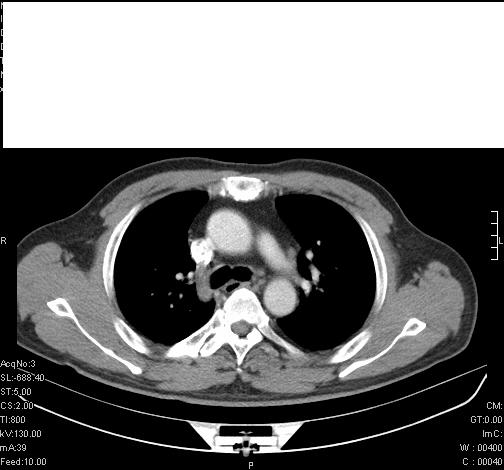

标题: CT6685:右肺阻塞性炎症,增强CT。

前几天,发了患者的平扫片,患者抗炎一周后增强扫描。右中叶病灶吸收明显,但下叶病灶未见明显吸收。右肺门可见结节影,看来凶多吉少

右肺下叶支气管管腔狭窄,管壁增厚,右下肺见斑片状高密度影,考虑右侧肺门中心肺癌伴阻塞性肺炎

右肺下叶支气管壁明显增厚,考虑癌症并阻塞性炎症、肺门淋巴结肿大

考虑右肺癌并阻塞性炎症、肺门淋巴结肿大

还是考虑右肺中央型肺癌可能性大

右肺下叶支气管壁不规则增厚,右肺下叶有斑片状影分布。考虑右肺中央型肺癌伴右肺下叶阻塞性改变。建议支纤镜检查。平扫比增强较好显示了病变情况。

考虑右肺中央型肺癌可能性大

右主支气管狭窄,管壁增厚。考虑右中心性肺ca伴阻塞性肺炎。